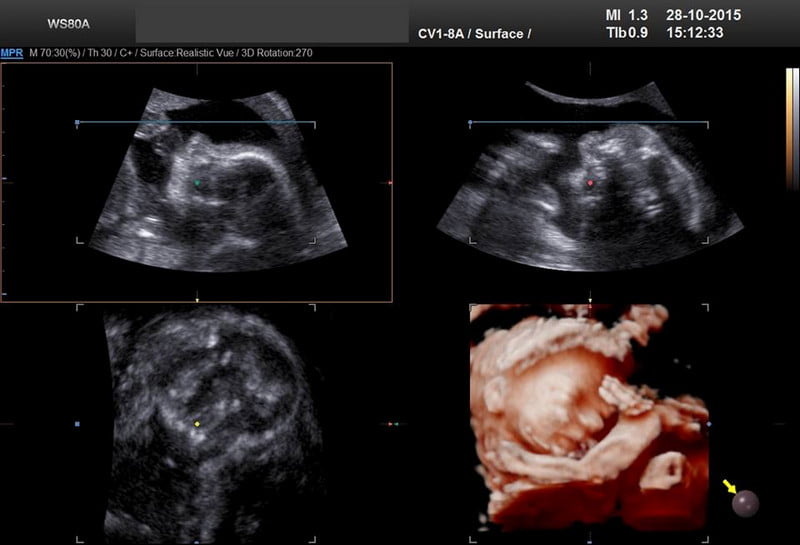

Ecografia 3D – o procedură medicală esenţială pentru femeile însărcinate

Cunoscută şi sub denumirea de ecografie morfo-fetală, ecografia 3D este recomandată tuturor femeilor însărcinate. Vorbim despre o tehnică modernă de imagistică medicală ce permite medicului